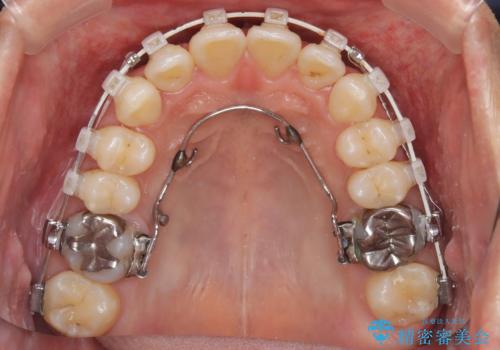

- 矯正装置

- 審美装置

上顎はリンガルアーチにて遠心移動を行うことで前歯を唇側傾斜させずに配列することができました。